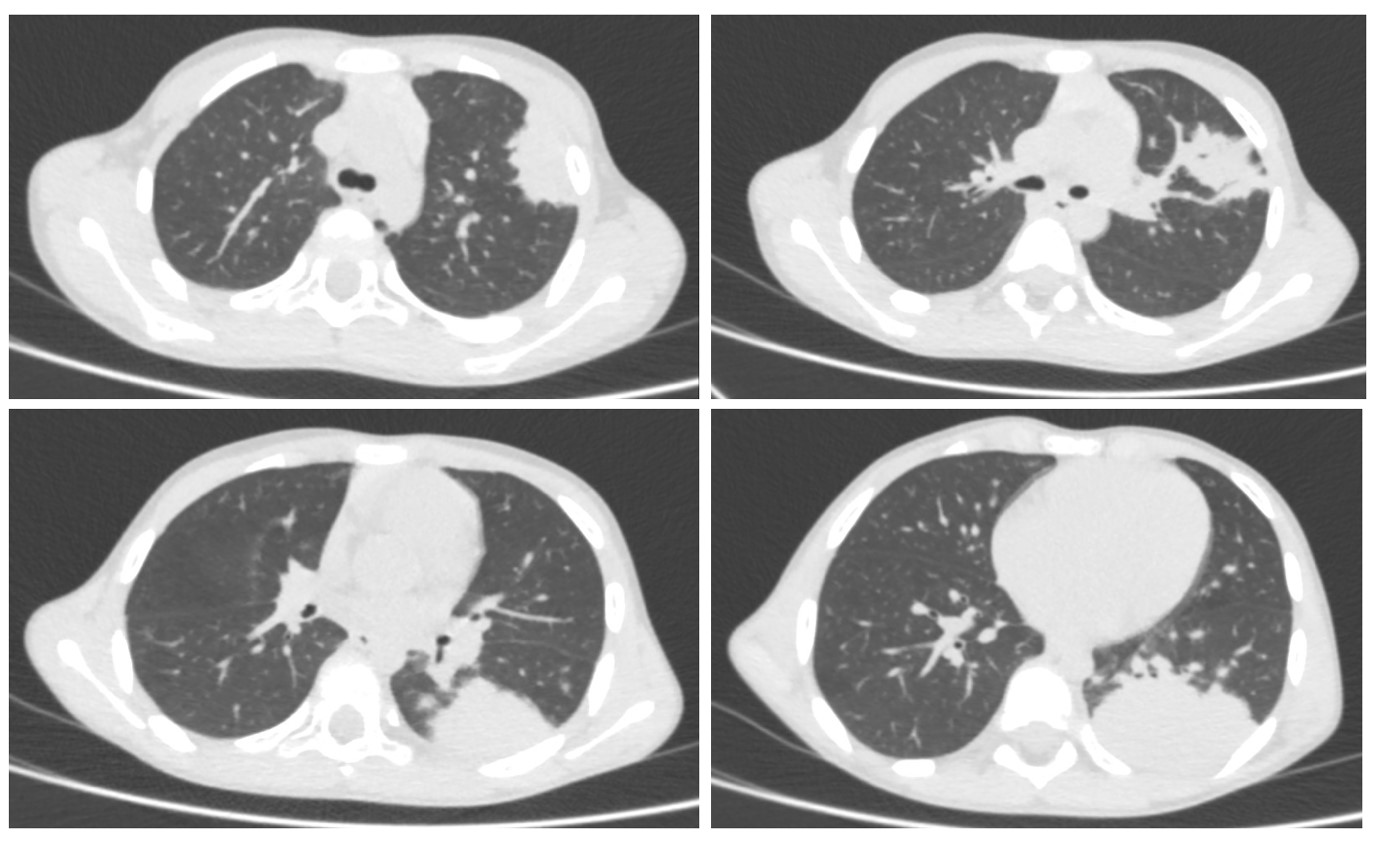

С учетом высоких маркеров воспаления, болевого синдрома, округлого затемнения на рентгенограмме органов грудной клетки с целью дифференциальной диагностики с абсцессом легкого принято решение о проведение компьютерной томографии (КТ) органов грудной клетки. При проведении КТ органов грудной клетки (от 15.12.2024) в S3, S6, S10, S9 левого легкого определяются две крупных зоны уплотнения легочной паренхимы. Структура их гомогенная, солидная, с небольшими участками воздушной бронхограммы, контуры достаточно четкие, местами тяжистые. Нижняя зона прилежит к париетальной плевре на уровне задних отрезков VII–X ребер, верхняя зона на уровне переднего отрезка 2 межреберья. Правое легкое во всех отделах без нарушения воздушности. Трахея и крупные бронхи не изменены. Плеврального выпота не выявлено (рис.2).

Рисунок 2 - КТ-картина соответствует левосторонней полисегментарной пневмонии